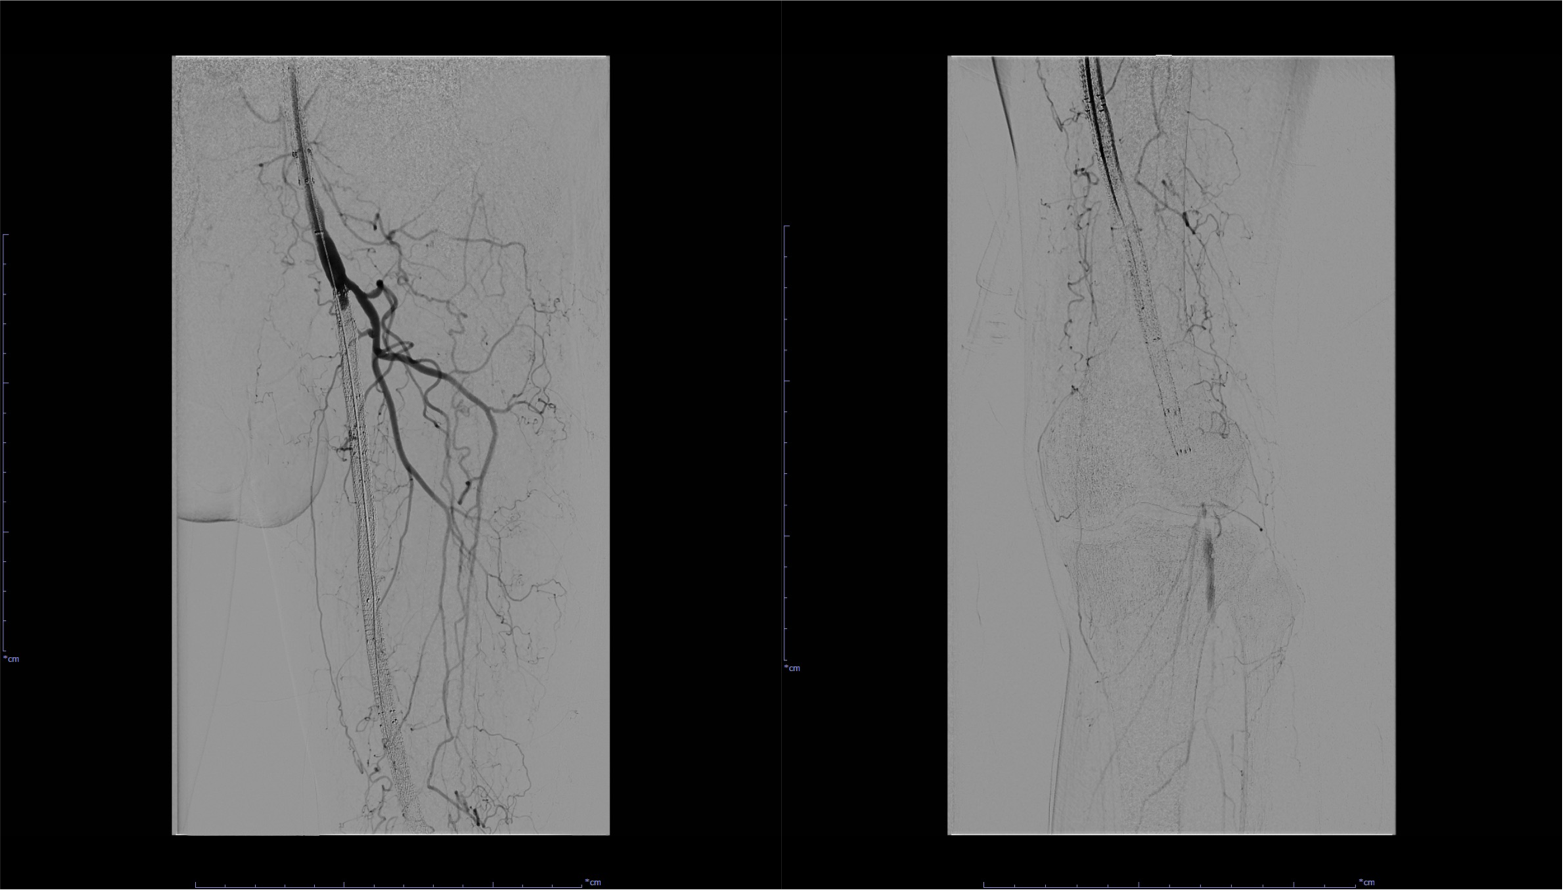

図4.左SFA~Pop. A血管造影(治療前)

左SFA~Pop. Aステント内およびステント遠位部の閉塞が認められる